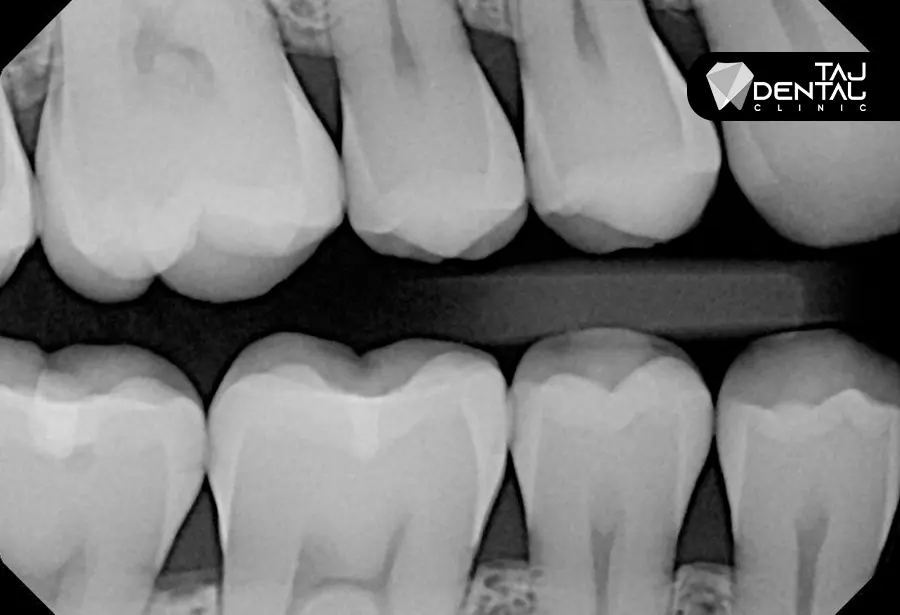

رادیوگرافی بایت وینگ نوعی رادیوگرافی دندانی است که برای به دست آوردن تصویری دقیق از سطوح بین دندانی استفاده میشود. این تکنیک شامل گرفتن تصاویری از دندانهای بالا و پایین به صورت همزمان است، که امکان بررسی فضاهای بین دندانی و مناطق پنهانی که ممکن است دچار پوسیدگی شوند را فراهم میکند.

این نوع تصویربرداری از یک قطعه کوچک (بایت وینگ) استفاده میکند که بیمار آن را گاز میزند. این ابزار باعث میشود که دندانها و لثهها در یک زاویه مناسب برای عکسبرداری قرار گیرند. این تصاویر بیشتر برای تشخیص پوسیدگیهای دندانی و بررسی سلامت لثهها مورد استفاده قرار میگیرد.